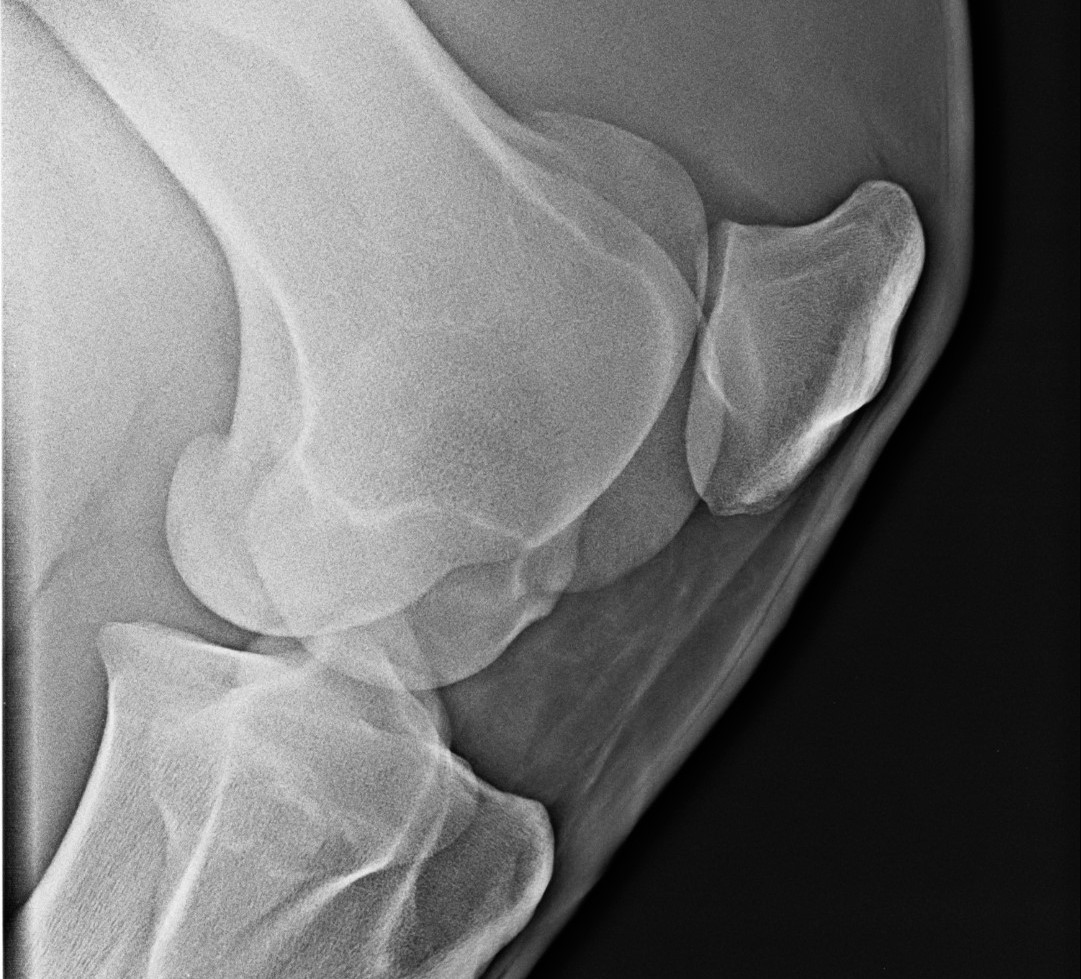

Számunkra legfontosabb alkalmazása a sántaságvizsgálathoz kapcsolódik. Miután megállapítottuk, hogy melyik testrész fájdalmas, megröntgenezzük az adott területet. Fontos tudni, hogy egy felvétel ilyenkor nem elég, legalább kettő, de inkább négy-hat, különböző irányú röntgenkép elkészítése is szükséges lehet.